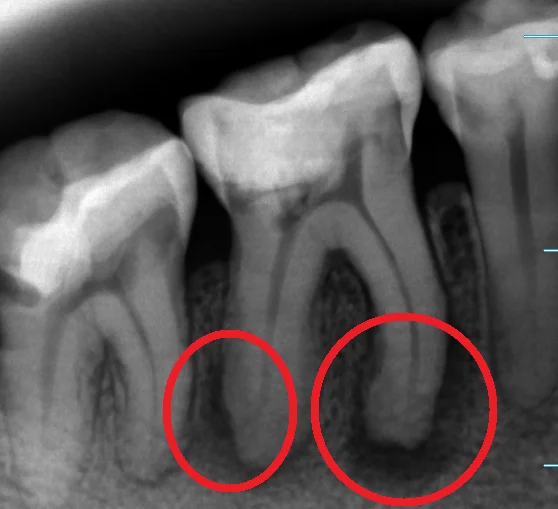

この赤丸で囲んでいる黒くなっているところが、骨が溶かされて膿が溜まっている状況の所です。